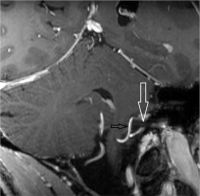

Abbildung 1: 7-Tesla-MRT mit Darstellung einer Gefäßschlinge (AICA, schwarzer Pfeil) um den N. vestibulocochlearis (weißer Pfeil) bei einem Patienten mit vestibulärer Paroxysmie.